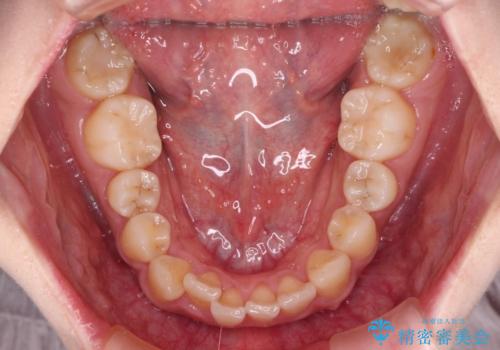

- 前歯の捻れを気にして来院された患者様です。

上顎前歯が捻れて前方に飛び出しており、下顎前歯もそれに沿うようにデコボコとなっていました。

IPR(歯と歯の間を削る処置)によりスペースを獲得して下顎前歯のデコボコを改善し、上顎前歯は下顎前歯と接する位置にまで引っ込めるように設定し、インビザラインにて矯正治療を行うこととしました。

しっかりと装着時間を守ってくださったので、予定通り1年強で治療を終えることができました。